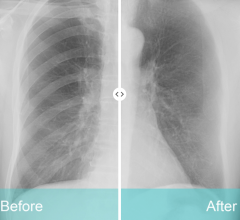

March 22, 2023 — The Riverain Technologies ClearRead Bone Suppression solution is now available on the Siemens ...

March 20, 2023 — A study by Emory Healthcare reports that Konica Minolta Healthcare’s Dynamic Digital Radiography (DDR) ...